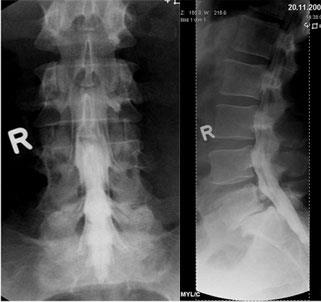

Aufnahmen von der Wirbelsäule zur Beurteilung von Veränderungen am Knochen, vor Operationen, zum Ausschluß von Knochenbrüchen und zur Verlaufskontrolle. Eine spezielle Vorbereitung der Patienten ist nicht notwendig. Moderne Röntgengeräte fertigen solche Aufnahmen mit einer geringen Strahlendosis an. Für alle, die sich genauer über die Auswirkung von Strahlen informieren wollen, empfiehlt sich ein Blick in Wikipedia.

Dies sind Röntgenaufnahmen von derselben Stelle, die in verschiedenen Körperpositionen aufgenommen werden, bei der Wirbelsäule zumeist in Vor- und Rückneigung. Sie dienen der Diagnose von Gleitwirbeln.